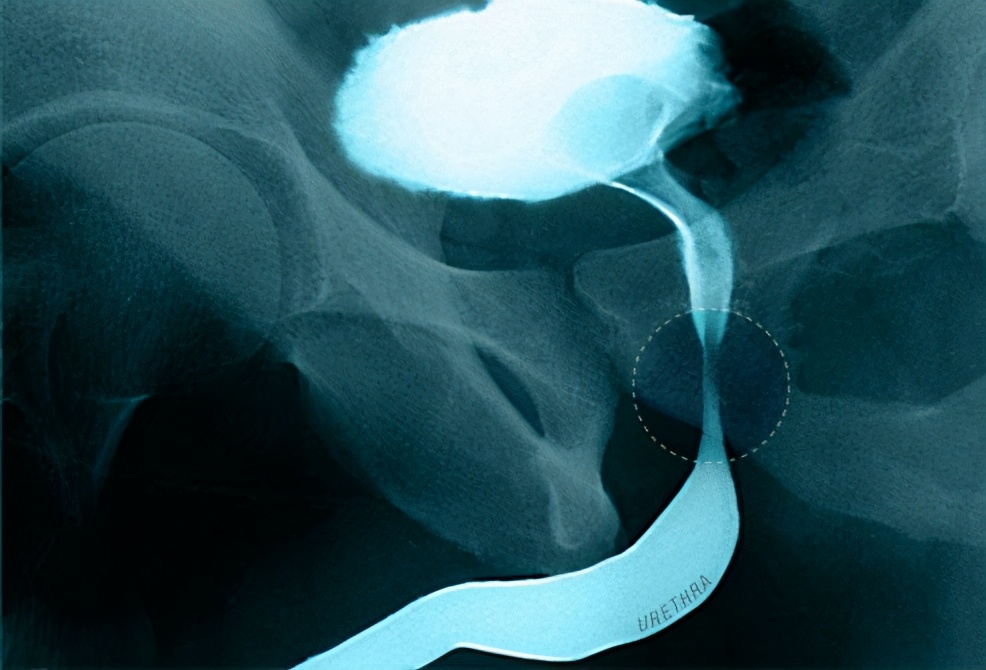

当前列腺增大到完全堵塞尿道(如图)或出现膀胱感染的时候人就会出现无法排尿的症状。膀胱肌肉也可能变得太弱而不能通过收缩将尿液挤出。